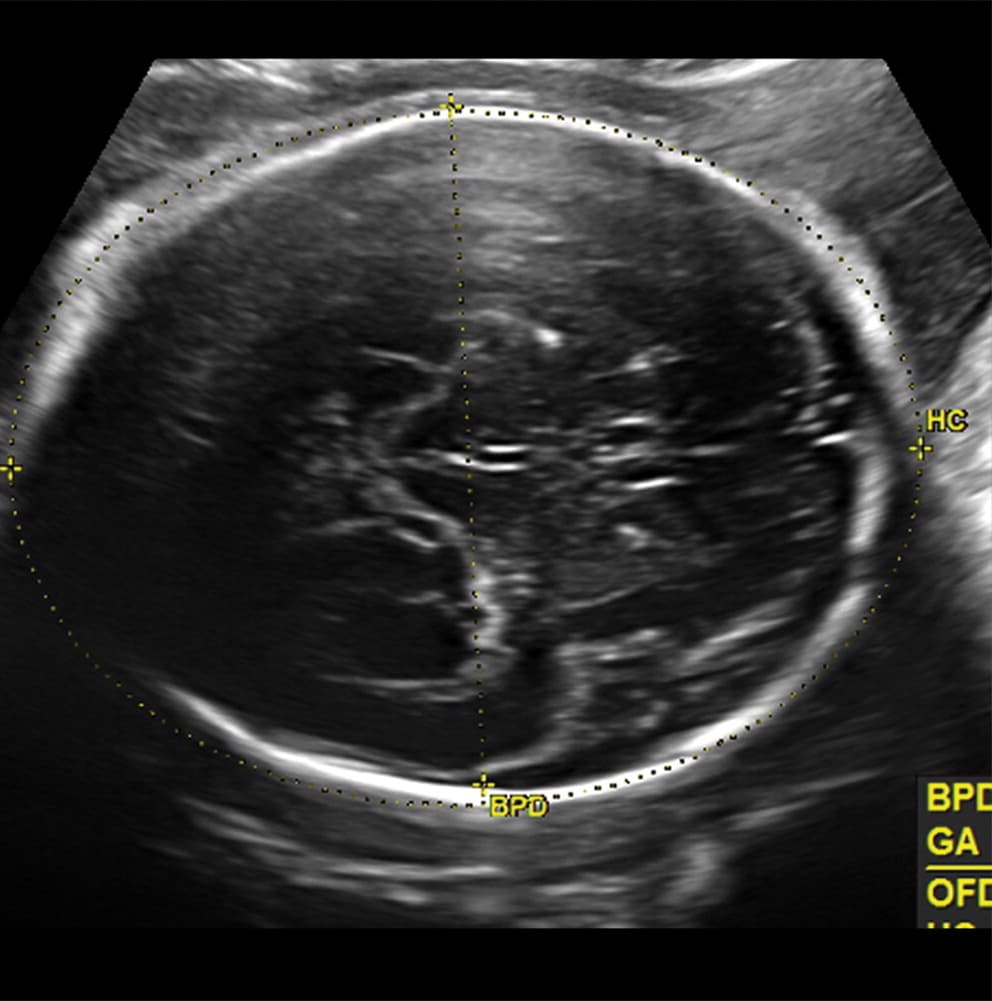

Investigadores brasileños difundieron este martes el mayor número hasta ahora disponible de imágenes computarizadas, resonancias magnéticas y ultrasonidos, de bebés y fetos infectados con el virus del Zika. El daño es mucho mayor del que anticipaban.

Así describe la radióloga brasileña Fernanda Tovar-Moll lo que vio al analizar centenares de imágenes computarizadas, resonancias magnéticas y ultrasonidos de 45 bebés que se contagiaron de zika en el vientre materno en el estado de Paraíba, en el noreste del país, donde el brote ha sido severo.

Todavía se desconoce exactamente cómo el zika logra penetrar la placenta y contagiar al feto, cuando la mayoría de los víruses no lo consigue. Tampoco el por qué solo algunas mujeres embarazadas que están infectadas de zika transmiten el virus a su feto. Pero se cree que el daño mayor ocurre durante el primer trimestre. “A las 20-24 semanas ya se pueden ver la mayoría de las anomalías en un ultrasonido”, comentó Tovar-Moll.